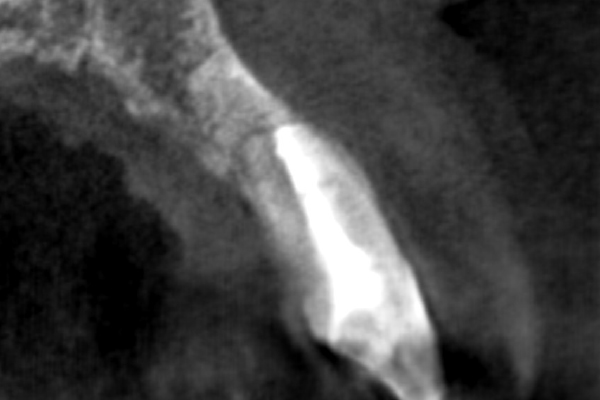

【札幌駅前】精密根管治療

30代男性の小臼歯(奥歯)の症例

- 主訴

- 「奥歯で咬むと違和感がある」「時々歯茎が腫れる」とのことでご来院されました。数週間前から症状があり、他の医院では「抜歯の可能性がある」と言われ、不安に感じていらっしゃいました。

- 期間

- 治療期間2ヶ月、治療回数3回、レントゲン写真で治癒を確認できるまでの期間6ヶ月

- ●精密根管治療(小臼歯)121,000円(税込)

- 治療内容

- 1.古い被せ物の除去と虫歯の徹底除去

まず、古い銀歯を外し、内部に広がっていた虫歯を丁寧に取り除きました。

2.マイクロスコープ下での根管治療

唾液などによる細菌の侵入を防ぐ「ラバーダム」を装着し、マイクロスコープ(歯科用顕微鏡)で根管内を数十倍に拡大しながら治療を進めました。複雑な形状の根管の内部まで、汚染された組織を徹底的に洗浄・消毒します。

3.根管充填(こんかんじゅうてん)

根管内が完全にクリーンになったことを確認し、再感染を防ぐために専用の薬剤で隙間なく密閉しました。

4.土台と被せ物の作製

歯の強度を補うための土台を立て、最終的なセラミックの被せ物を作製し、装着しました。

- 治療に伴うリスク

- 少しでも汚染物質が残ると再発のリスクが高まります。